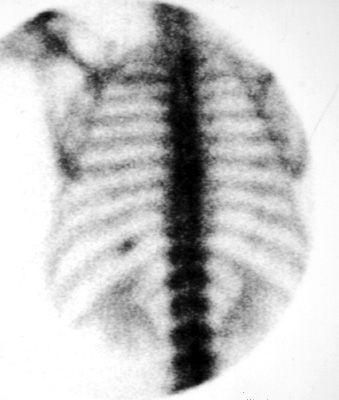

Bone scans can be used to localized specific lesions for biopsy. This is most often used to localize rib abnormalities. The position of the lesion is marked on the skin using a lead marker. After the portion of the bone has been removed, the piece can be reimaged to confirm that the abnormal portion of the bone was removed.

Note the lesion in the posterior left 10th rib.

The abnormality has been covered with a round piece of lead. Note the "cold" spot which results,

This is the portion of the rib which was removed. Note the hot spot at the top of the bone fragment.